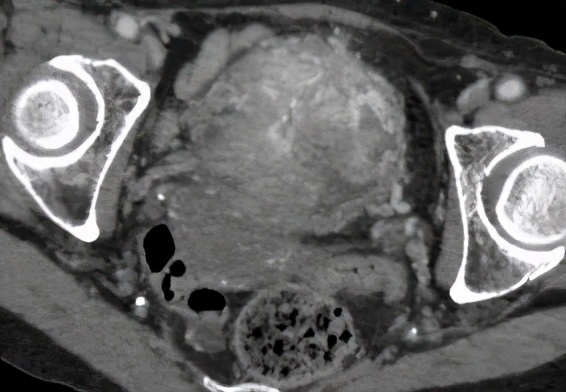

87岁的老太太,突然无诱因的下腹痛,伴血尿、血凝块,来我院治疗。经过CT增强检查发现膀胱巨大肿瘤。

CT结果见膀胱旁一巨大肿瘤